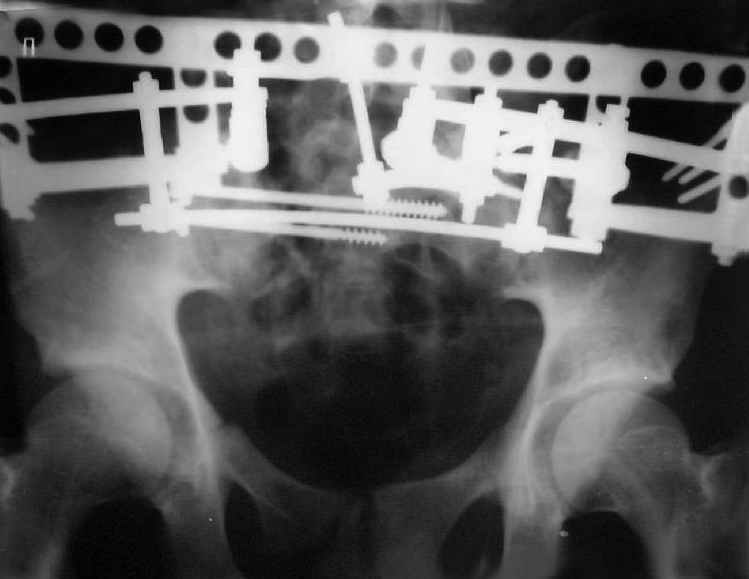

Для информации к размышлению о возможности исправления имеющейся деформации предлагаю похожий случай.